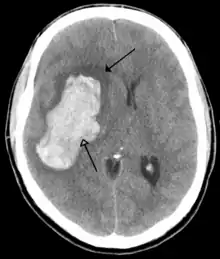

| CT scan of the brain showing a prior right-sided ischemic stroke from blockage of an artery. Changes on a CT may not be visible early on.[1] | |

The main risk factor for stroke is high blood pressure.[6] Other risk factors include tobacco smoking, obesity, high blood cholesterol, diabetes mellitus, a previous TIA, end-stage kidney disease, and atrial fibrillation.[2][6][7] An ischemic stroke is typically caused by blockage of a blood vessel, though there are also less common causes.[12][13][14] A hemorrhagic stroke is caused by either bleeding directly into the brain or into the space between the brain's membranes.[12][15] Bleeding may occur due to a ruptured brain aneurysm.[12] Diagnosis is typically based on a physical exam and supported by medical imaging such as a CT scan or MRI scan.[8] A CT scan can rule out bleeding, but may not necessarily rule out ischemia, which early on typically does not show up on a CT scan.[9] Other tests such as an electrocardiogram (ECG) and blood tests are done to determine risk factors and rule out other possible causes.[8] Low blood sugar may cause similar symptoms.[8]

For diagnosing ischemic (blockage) stroke in the emergency setting:[64]

- CT scans (without contrast enhancements)

- sensitivity= 16% (less than 10% within first 3 hours of symptom onset)

- specificity= 96%

For diagnosing hemorrhagic stroke in the emergency setting:

- CT scans (without contrast enhancements)

- sensitivity= 89%

- specificity= 100%

CT scans may not detect an ischemic stroke, especially if it is small, of recent onset, or in the brainstem or cerebellum areas. A CT scan is more to rule out certain stroke mimics and detect bleeding.[9]